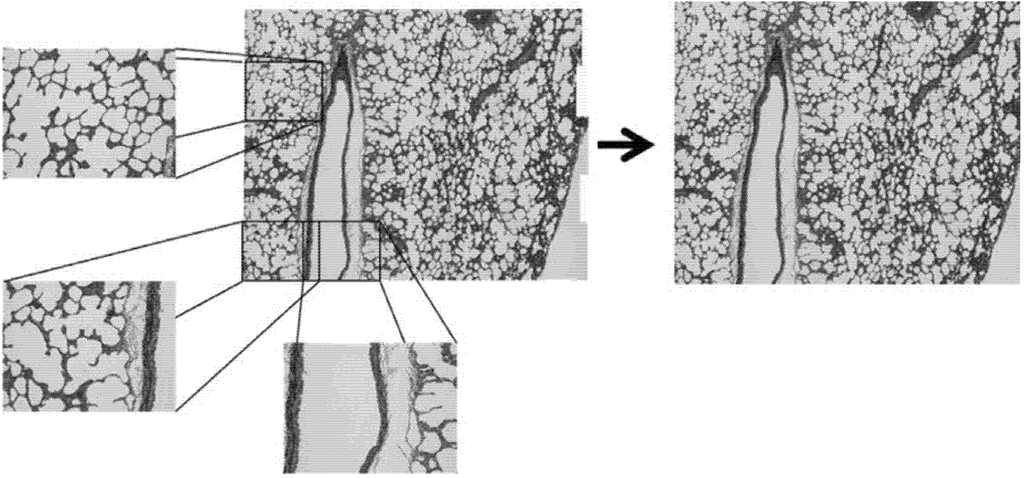

Specimens were quantitatively analyzed for differences in microstructure using ImageJ (National Institute of Health, Bethesda, MD, USA). For each orientation, a series of twenty five overlapping light microscope images were obtained. These micrographs were compiled using the MosaicJ plugin (Ecole Polytechnique Federale De Lausanne, Lausanne, Switzerland) for ImageJ. Briefly, overlapping micrographs were positioned within the MosaicJ window and the software was used to create a single cohesive image based on overlapping portions of separate micrographs. This allowed for larger regions of the slide-mounted sample to be imaged without omitting portions of larger alveoli. The cohesive images were then cropped to create the largest rectangle available. Figure 2 illustrates how individual micrographs contributed to the composites, and how the uneven edges were cropped. The final composites for each direction were thresholded, inverted, and analyzed using the “Analyze Particles” feature in ImageJ. In this tissue the most relevant, and most readily observed by this method, feature is the alveolar spaces (white) of the lung tissue. “Analyze Particles” was configured to filter out particles with an area of less than 2000 pixels, approximately 2839 square microns, to eliminate extremely small particles or artifacts. Edge particles were also filtered. Roundness, Circularity, Solidity, and Aspect Ratio of the Fit Ellipse were plotted as histograms and analyzed to discern the 1st, 2nd and 3rd quartiles of the histograms to compare any differences among the alignment planes. These parameters describe particle shape and provide insight into particle elongation and tortuosity. Formulas for these parameters are shown in Appendix.

Figure 2. Composite micrograph composed of individual micrographs.

Micrographs for each anatomical plane are presented in Figure 5. Figure 5A-B, C-D, and E-F show Movat’s Pentachrome for the sagittal, frontal, and transverse planes, respectively. These micrographs do not indicate any apparent qualitative differences in morphology or alignment of microstructural features among the three anatomical planes. Composite Micrographs created with MosaicJ are shown in Figure 6; Figure 6A is sagittal, Figure 6B is frontal, Figure 6C is transverse. The corresponding histograms for a particle analysis, particles being alveolar spaces, are shown in Figure 7. Histograms for Roundness (Figure 7A), Circularity (Figure 7B), and Solidity (Figure 7C), were prepared with bins from 0 to 1, incremented by 0.05, where the columns indicate the percentage of particles that fell into each bin. The aspect ratio (Figure 7D), was prepared with bins from 1.0 to 3.4, incremented by 0.1, and columns denoting the percentage of particles for each bin. It should be noted that some aspect ratio data was not displayed in this histogram in the interest of more effectively highlighting the majority of the data; 3.4 was chosen as the end of the axis because this was the final value at which more than two particles occurred within a single bin for any of the three alignments. Table 1 shows the 1st quartile, median, and 3rd quartiles for the histograms. Histograms of particle analysis parameters had little difference among the different orientation planes.

Figure 6. Composite micrographs of (A) saggital, (B) frontal, (C) transverse planes (200 μm scale).